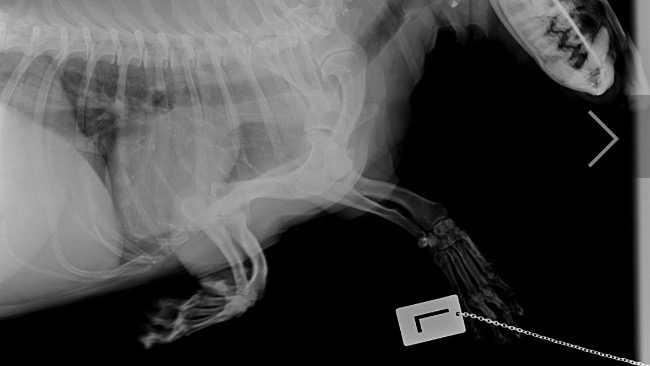

Als es scheindass sich sein Gesundheitszustand endlich stabilisiert, hatte Czaruś ein Unfall. Letzten Sonntag wurde er von einem Auto angefahren. Er wurde notfallmaßig in eine Tierklinik gebracht wo er noch am selben Tag zwiemal untersucht und diagnostiziert wurde. Er wurde außerdem am eine spezialisierte ortopedische Klinik überweisen - er hat bereits eine konsultation bei einem wunderbaren Tierarzt der Klinik Dr Hau erhalten. Leider erlitt Czaruś schwere Fakturen im Beckenbereich - Brüche des Schambeins, des sitzbeins , der linken Hüftpfanne sowie eine Bruch und Riss des linken Oberschenkelknochens.